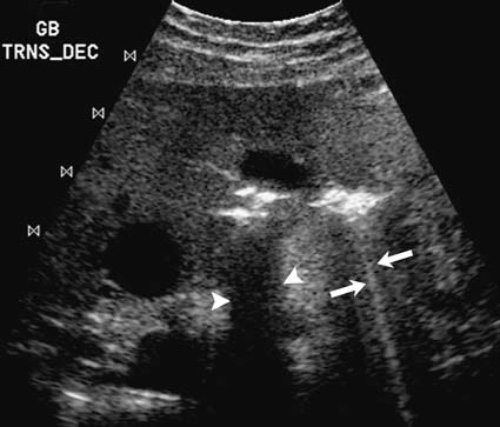

Этот артефакт представляет собой вариант артефакта реверберации, и обусловлен он, как правило, наличием пузырьков газа. Когда звуковые волны взаимодействуют с пузырьками газа, происходит возбуждение жидкости, находящейся между этими пузырьками, в результате чего появляется резонанс. Такой эффект дает большое количество ложных эхо, расположение которых кажется глубже истинного эхо. На практике артефакт множественного отражения используют для диагностики внутрибрюшного свободного газа (рисунок 2).

Рисунок 2. Газы, отражая звуковые волны, могут образовывать тени с четкими границами (см указатели). Реверберация звука внутри газовых пузырьков образует артефакт множественного отражения (см стрелки)